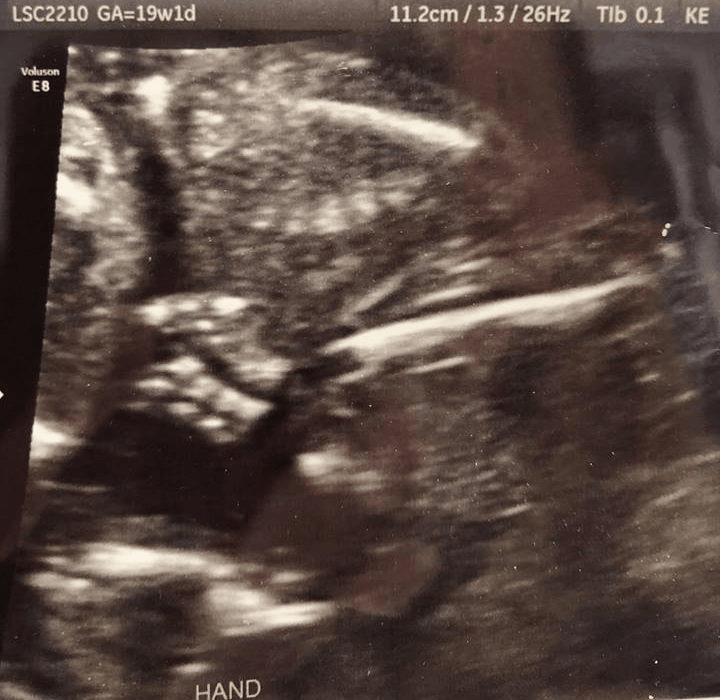

The majority of miscarriages occur within the first twelve weeks of pregnancy, but it’s not uncommon for miscarriages to occur up until 20 weeks. (After 20 weeks a pregnancy loss is referred to as a stillbirth.) As she struggled to complete her family, Everton had three first-trimester losses and a second-trimester loss, which was picked up during the 20 week scan. Everton recalls sitting with her husband in the waiting room, excitedly finalising their list of baby names in expectation of the gender reveal. Minutes later, the sonographer gently explained that there was no longer a heartbeat. “I remember feeling like the room was crashing. It felt like everything was just closing in on me.”